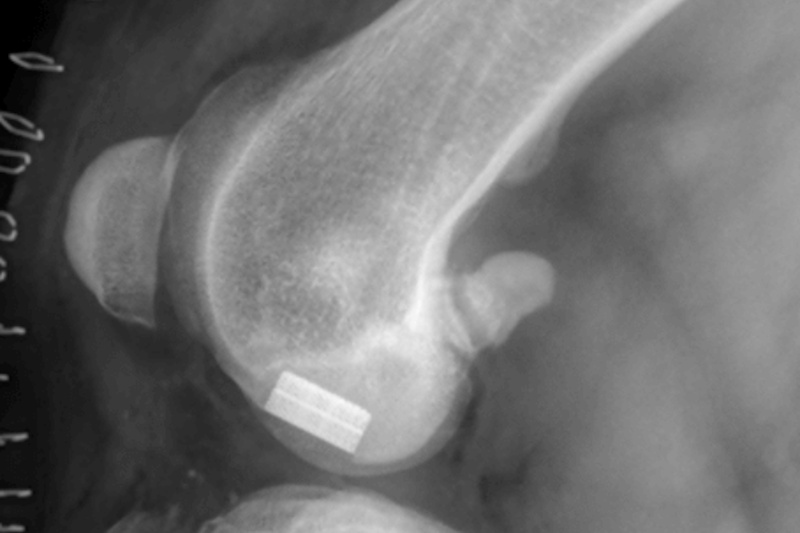

Coxofemoral Luxation (Hip Dislocation)

Hip Dislocation in canines